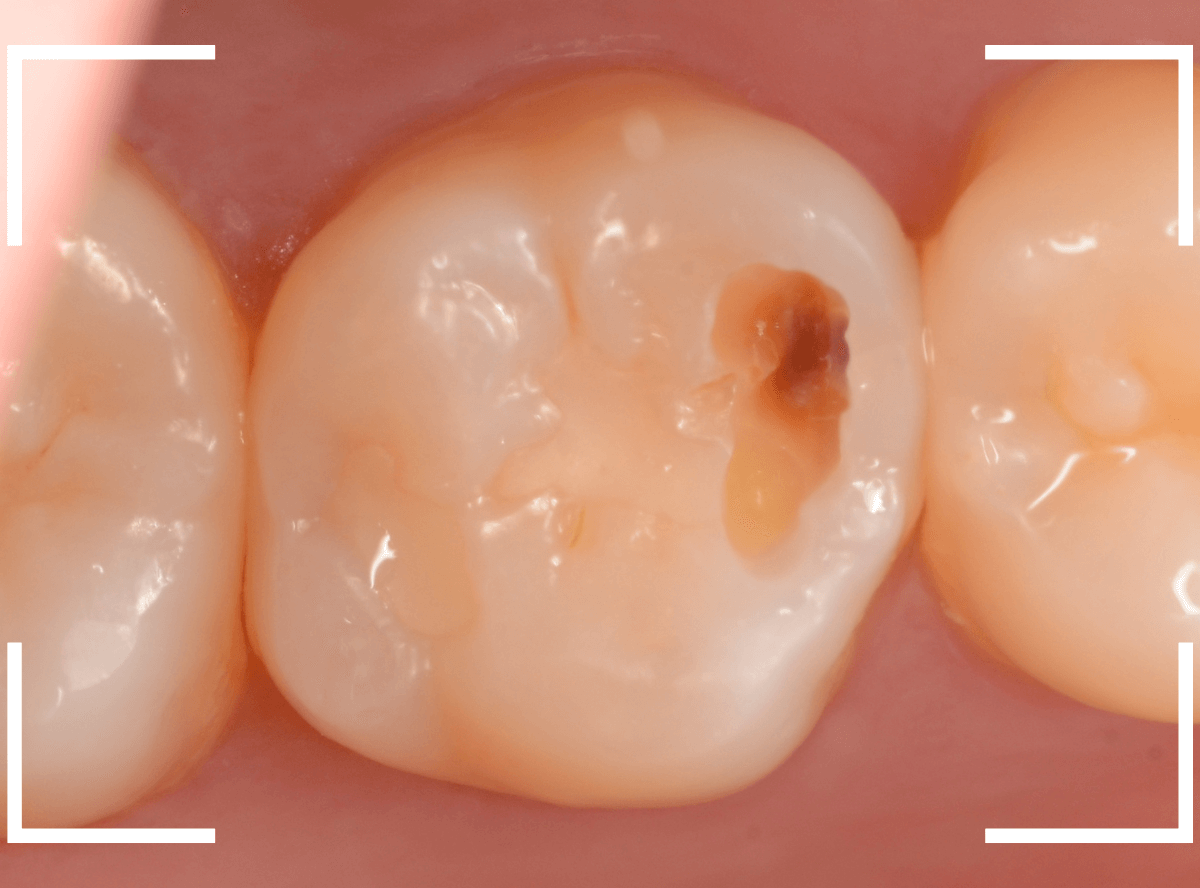

上の奥歯の虫歯が見つかった患者さんです。

初診のチェックの際に、上から目視すると、レジンがつめてある〇部分が薄暗く黒くなっているので、これは虫歯があるな、とわかりました。

治療を開始します。

先ほどの黒く見えた部分は少し削るとすぐに虫歯が出てきました。